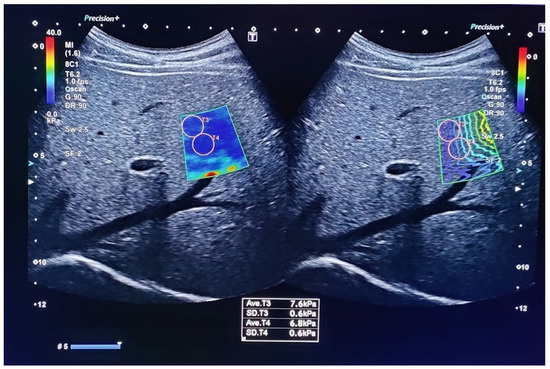

The measurement starts with a good visualization of the target organ with classical imaging. Next, the appropriate software is switched on at the desired location within the organ and points at it with the indicator, as presented in Figure 2. Several elasticity areas within the organ are measured and the mean or median value of measurement is provided using speed (m/s) and pressure (kPa) modules, both describing tissue’s elastic properties. The quality of the measurement is ensured by the manufacturer’s instructions.

Figure 2. Ultrasound elastography using Canon aplio-a with maintenance of quality control by obtaining a standard deviation of less than 20% of the measurement as well as by maintaining an IQR/median ratio <30%.